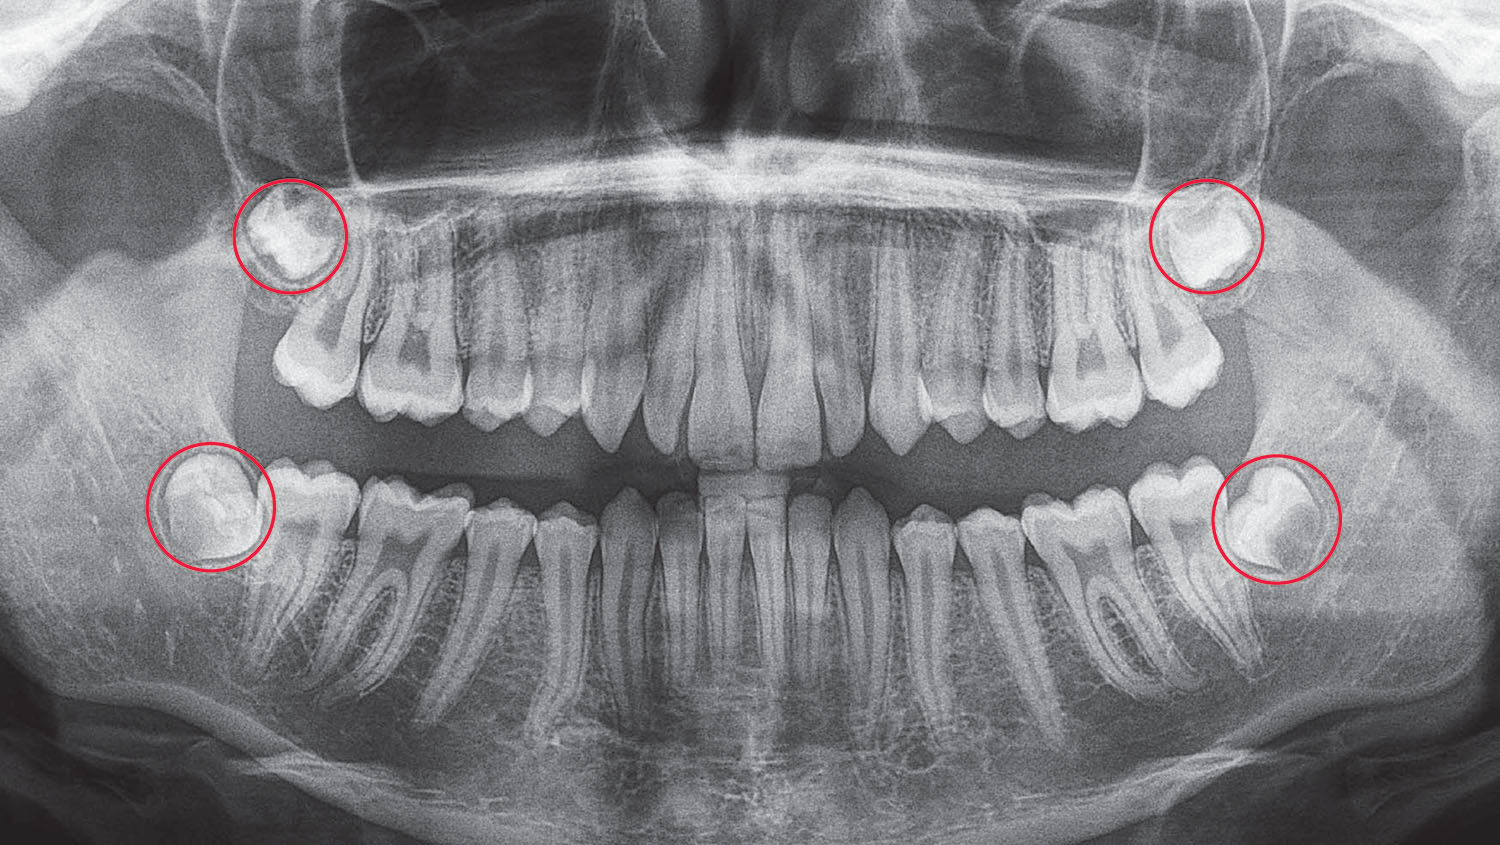

What Are Wisdom Teeth?

Wisdom teeth (third molars) are the last teeth to develop, usually appearing between ages 17–21. Most people have four wisdom teeth.

Because our jaws are generally smaller than those of our ancestors, wisdom teeth often do not have enough room to come through properly. This lack of space can lead to:

- Stay trapped under the gum (unerupted)

- Come through part way (partially erupted)

- Push into the tooth in front (impacted)

- Grow at the wrong angle (malaligned)

When this happens, issues are likely over time. Early assessment and removal can help prevent pain, infection, and other complications.

- Panoramic X-Ray (if required): $59

- 3D CBCT (if required): $79